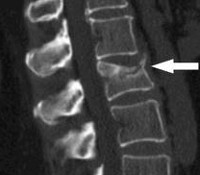

На спондиллограммах, КТ-, МРТ-сканах определяются различной степени повреждения позвоночника и структур спинного мозга.

КТ и МРТ проводятся в трех стандартных проекциях: сагиттальной, фронтальной и аксиальной + КТ с 3D реконструкцией.

Наличие в анамнезе травмы позвоночника и спинного мозга, характерная клинико-неврологическая симптоматика (болевой синдром в месте повреждения, проводниковые и сегментарные неврологические нарушения) и изменения на спондиллограммах, КТ и МРТ-сканах (переломы, вывихи, переломо-вывихи, растяжения костно-связочных структур позвоночника, изменение интенсивности сигнала спинного мозга) исключает необходимость в проведении дифференциального диагноза.

Диагноз устанавливается на основании характерного анамнеза, симптомов и результатов рентгенографии позвоночника. Снимки выполняются в двух проекциях, наиболее информативна боковая проекция. На рентгенограмме выявляется снижение высоты и клиновидная деформация одного или нескольких позвонков. При необходимости для оценки состояния спинного мозга и его оболочек, а также связок и хрящей позвоночника, назначают МРТ или КТ позвоночника. При наличии неврологических нарушений больного направляют на консультацию к неврологу или нейрохирургу. Для выявления и более точной оценки степени повреждения спинного мозга применяют миелографию.